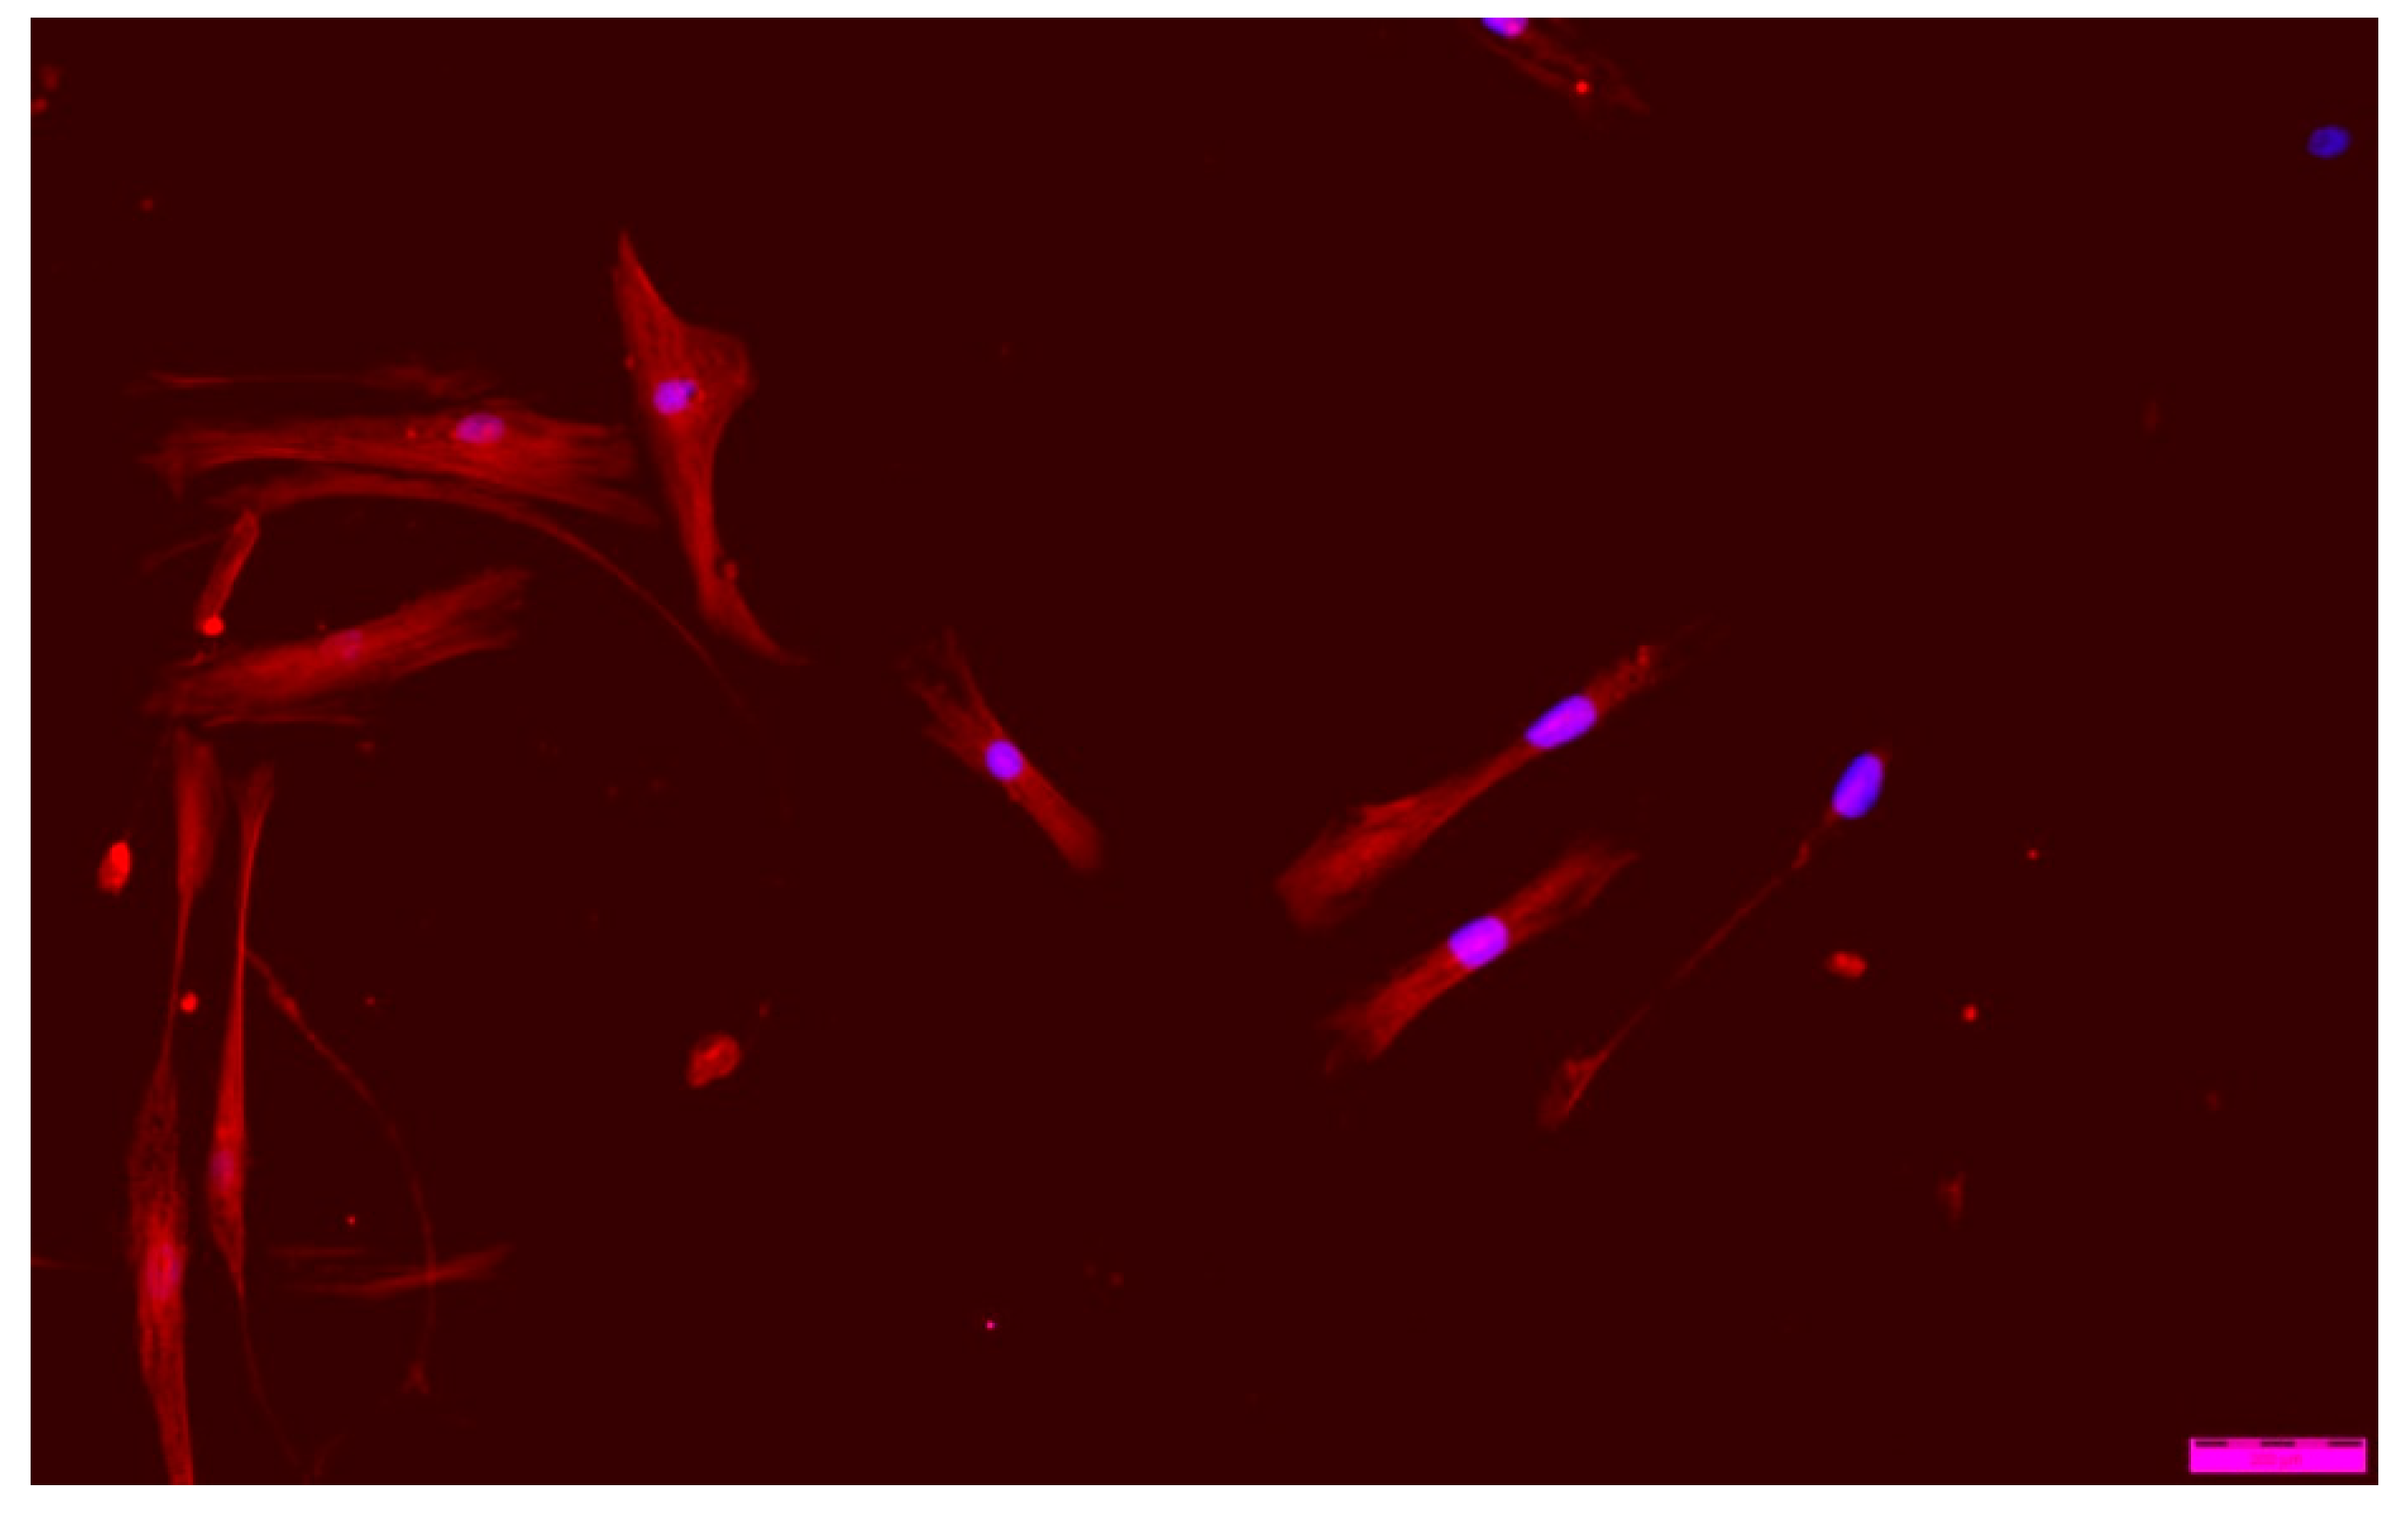

When analyzing ‘cell’ morphology using fluorescence microscopy, it was observed that cells grown in the presence of ALG-PFC and (ALG-PFC)net membranes show the correct morphological picture (Figure 12 and Figure 13). After six days of the culture, we observed numerous cells on the surface of glass coverslips coated with ALG-PFC and (ALG-PFC)net. In addition, the spindle-shaped cells of fibroblastoid features were present on both types of surfaces.

Figure 12. Fluorescence microscopy image of human fibroblast cells cultured in the presence of the alginate–perfluorooctyl (ALG-PFC) coating after a 6-day culture.

Figure 13. Fluorescence microscopy image of human fibroblast cells cultured in the presence of a cross-linked alginate–perfluorooctyl coating ((ALG-PFC)net) after a 6-day culture.